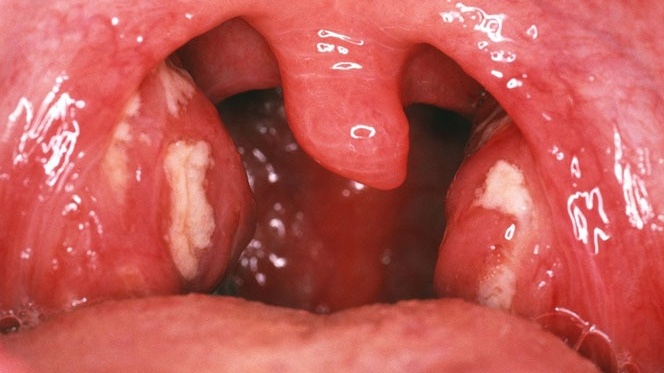

Hình ảnh viêm họng hạt mãn tính

Viêm họng hạt mãn tính là giai đoạn tiếp theo của bệnh khi không được điều trị dứt điểm. Hình ảnh viêm họng hạt trong giai đoạn này có sự khác biệt rõ rệt:

- Niêm mạc họng nổi các nốt đỏ li ti: Toàn bộ niêm mạc họng trở nên đỏ và có các nốt lympho sưng to. Kích thước các nốt lympho có thể bằng hạt gạo, hạt ngô.

- Hạt lympho gia tăng kích thước: Các hạt lympho có thể liên kết với nhau thông qua các mạch máu nhỏ, khiến vòm họng trông rất khác biệt.

- Amidan sưng: Các amidan có thể sưng phù, có thể xuất hiện các mảng mủ trắng.

Trong giai đoạn này, triệu chứng có thể không có sốt, nhưng các cơn ho sẽ trở nên dai dẳng hơn. Việc điều trị sẽ phức tạp và kéo dài hơn so với giai đoạn cấp tính.

Viêm họng hạt có mủ là tình trạng viêm họng hạt chuyển biến nặng, xuất hiện các nốt mủ trắng ở vòm họng. Hình ảnh điển hình bao gồm:

- Mủ trắng trên niêm mạc họng: Các nốt mủ trắng có thể xuất hiện trên amidan hoặc trên bề mặt niêm mạc họng.